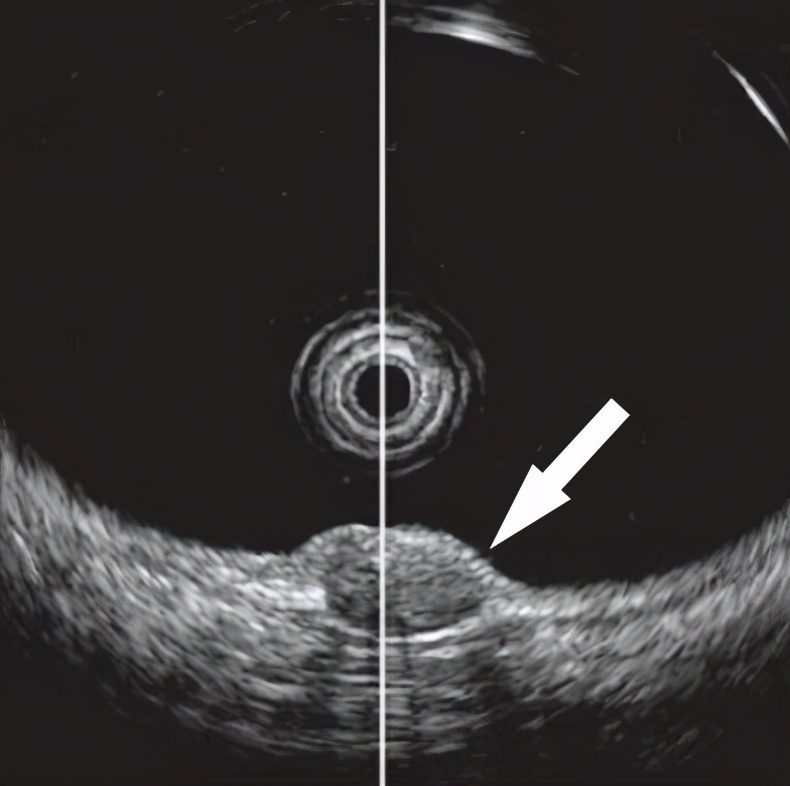

大肠类癌起病隐匿,多发于40~60岁,男性稍多于女性,常在检查肠道其他病变时被偶然发现或术后病理证实。90%发生于粘膜下层。微小大肠类癌多无症状;当瘤体增大后可出现便血、大便习惯改变、黏液脓血便和里急后重等不适;晚期大肠类癌与直肠癌表现相似。大肠类癌结肠镜下表现为粘膜下单一圆形肿物突向肠腔,广基隆起,边缘平或呈陡峭或亚蒂型隆起,黄色或苍白色外观(图20-1)。直径<2.0cm者表面多有正常粘膜覆盖,质地较硬,直径>2.0 cm者表面有时可见溃疡,容易误诊为侧方生长型息肉和大肠癌。小的大肠类癌,容易与小的大肠息肉混淆(图20-1)。大肠类癌在超声肠镜下表现为粘膜下层边界清晰、回声均匀的低回声结节(图20-2)。

图20-2:大肠类癌在超声肠镜下表现为粘膜下肿块。